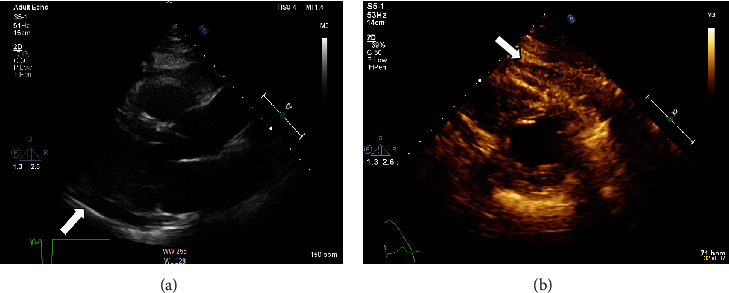

背景:新冠肺炎疫苗临床试验报告了mRNA疫苗(阿斯利康)帮助控制疾病的安全性和有效性。以前很少有报告显示与COVID-19疫苗相关的各种副作用,其严重程度各不相同。在接受我们报告的mRNA COVID-19疫苗的人群中观察到心包炎和心肌炎的可能性。急性炎症性心包炎在首次接种该疫苗后可能是一种罕见的症状,在COVID-19时代分享这种罕见的症状对于更好地管理和接种疫苗后的结果是有益的。案例演示。这是一例健康成人患者在接受阿斯利康COVID-19疫苗第一剂后出现急性炎症性心包炎伴少量心包积液的病例,除COVID-19 PCR阴性外,无其他提示其他病毒性疾病的症状。一名48岁的健康男性在接种第一剂新冠肺炎阿斯利康疫苗9天后出现。该症状始于接种疫苗后3天,当时他主诉进行性胸痛,伴有低烧和全身乏力,几天后出现用力性呼吸困难。诊断为急性炎症性心包炎伴少量心包积液,并给予相应治疗。一星期后,病人的临床表现明显改善,心包积液得以消除。39天后,急性心包炎的影像学表现明显好转。结论:目前正在进行的COVID-19疫情仍在调查中,尽管多种疫苗已被证明对COVID-19有效,但由于我们不断了解这种新型疾病,指南仍在定期修改。然而,我们报告了一例在首次接种阿斯利康COVID-19疫苗后出现独特临床表现的病例,在文献中尚未广泛报道,这可能有助于提高人们对COVID-19疫苗接种后可能诊断和炎症性心包炎可能性的认识。

Background: Clinical trials of the COVID-19 vaccine reported the safety and efficacy of mRNA vaccines (AstraZeneca) to help control the disease. Few previous reports have shown various side effects associated with COVID-19 vaccines that vary in severity. The possibility of pericarditis and myocarditis has been observed in people who have received an mRNA COVID-19 vaccine which we are reporting. Acute inflammatory pericarditis can be a rare presentation after receiving the first dose of this vaccine, and it is enriching to share such rare presentations in the era of COVID-19 for better management and outcomes after vaccination. Case Presentation. This is a case of acute inflammatory pericarditis with a small pericardial effusion after receiving the first dose of AstraZeneca COVID-19 vaccine in a healthy adult patient who had no other symptoms suggestive of other viral illness in addition to the negative COVID-19 PCR. A 48-year-old healthy male presented nine days after receiving the first dose of COVID-19 AstraZeneca vaccine. The symptoms started three days after the vaccine, when he complained of progressive retrosternal chest pain with low-grade fever and generalized fatigue, followed by exertional dyspnea after a few days. The diagnosis of acute inflammatory pericarditis with small pericardial effusion was established, and the patient was accordingly treated. One week later, the patient showed significant clinical improvement with the resolution of his pericardial effusion. After 39 days, there was a significant radiological resolution of signs of acute pericarditis.